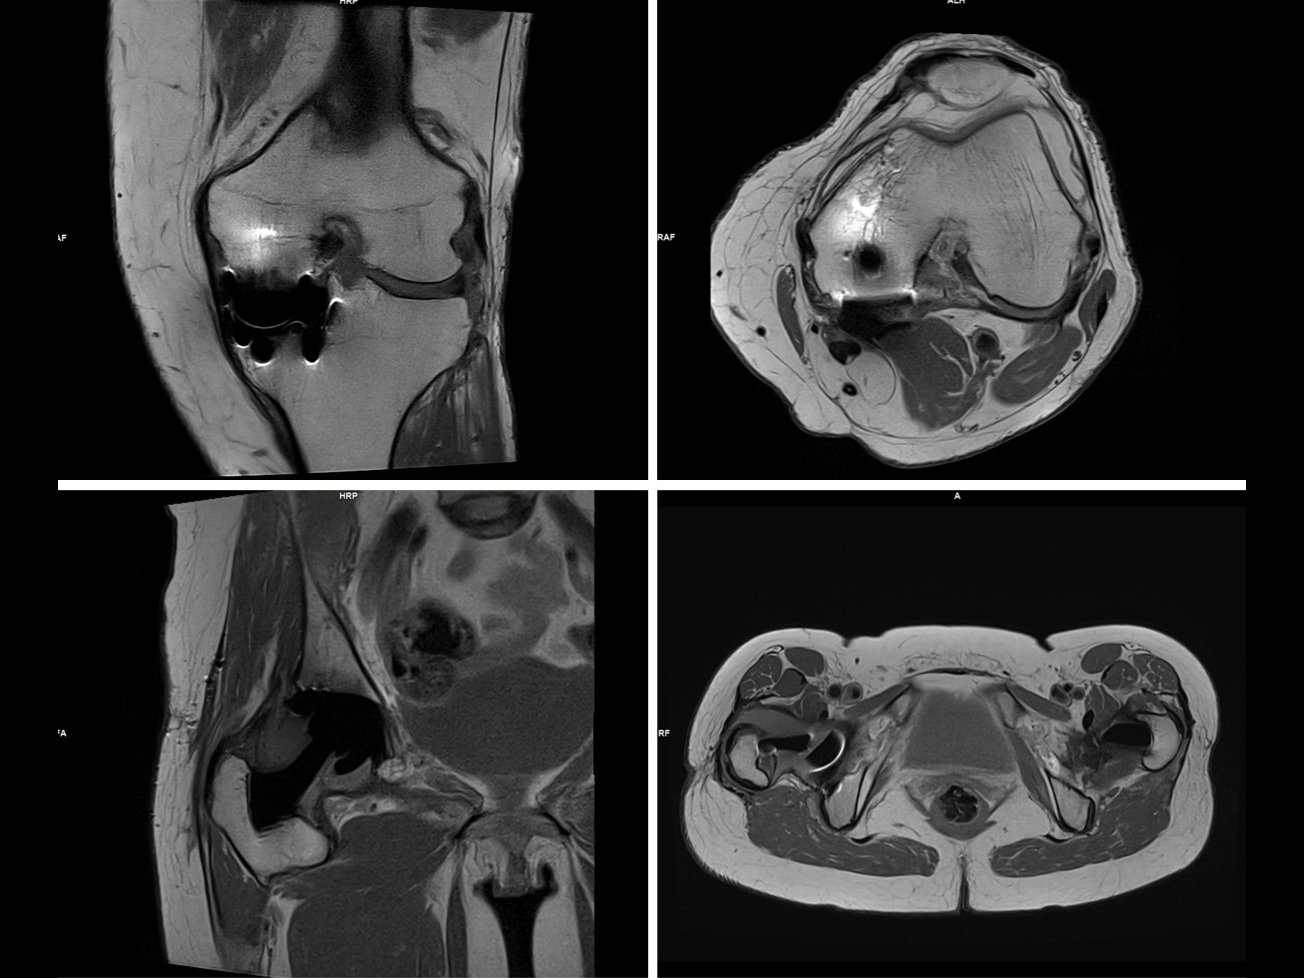

GOKnee2D and GOKnee2DSMS Protocols

Fast high-res 3D knee exams in 10 min. Download .exar1 files for MAGNETOM Aera and Skyra.